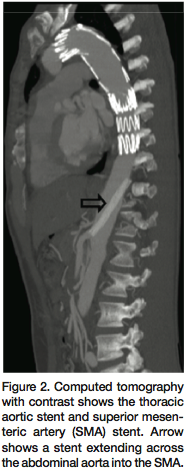

The patient was a healthy 36-year-old Hispanic male who presented with 5 days of lower back and abdominal pain. He noticed back pain while working at a construction site after he turned suddenly. At this time, he subsequently developed abdominal pain and was taken to an outside hospital and identified to have a descending aorta dissection with possible compromise of bowels. The patient was then transferred to our institution. At the time of admission, his white count was 30,000 and hemoglobin was 14. He had significant shift with 23 bands. His sodium was 128, potassium 3.3, chloride 87 with elevated liver enzymes and an amylase of 132 with a lactic acid of 3.3. At this time, he was not complaining of any lower extremity discomfort. On the left side, his pulses were completely intact. On the right side, they were present but decreased. He had some vague abdominal pain; however, he had received a significant amount of narcotics. He had no other complaints. A computed tomography (CT) scan of the chest, abdomen, and pelvis demonstrated a type B aortic dissection involving the celiac axis, SMA, and right renal artery (Figure 1). Diffuse small bowel dilatation seen on the CT scan was concerning for early small bowel ischemia.